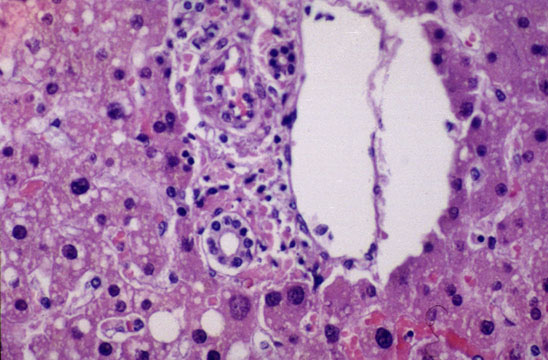

Fig 11 - SEPTAL BILE DUCTS

Located in the septal spaces at the confluence of few, 3-4, interlobular ducts are larger ducts measuring greater than 100 mu in diameter. They are normally surrounded by a concentric cuff of connective tissue and elastic fibers.